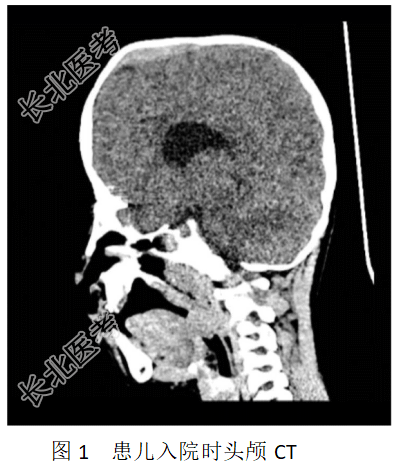

- [材料题] 患儿,男,6岁8个月,123cm,21kg,因“颅缝早闭术后5年余”入院。患儿足月顺产,Apgar评分不详。1岁时因“颅缝早闭”于我院行颅缝早闭外科手术矫治,术后恢复一般。入院查体:前额凸起,头部可见陈旧性手术疤痕,矢状缝稍凸起。双眼外凸、双手双足可及陈旧性瘢痕。头颅CT示:颅骨呈术后改变;上颌骨小,眼眶较浅,双侧眼球突出,颅内前后径小;C3-4椎间隙狭窄,附件融合畸形。其余检查未见明显异常(图1)。入院诊断为Apert综合征。